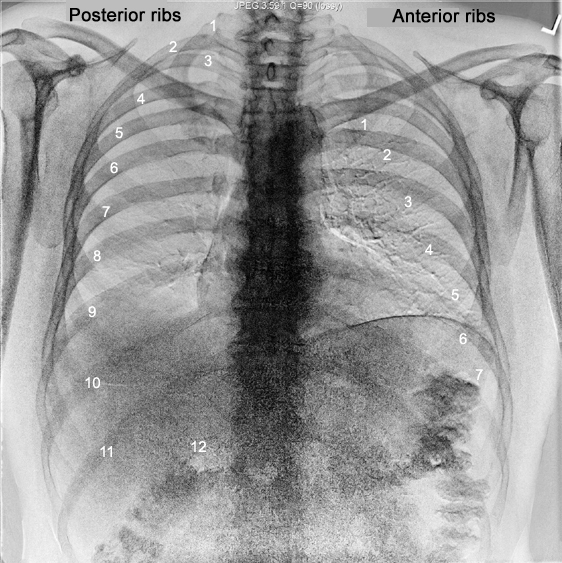

Evaluating The Chest Radiograph

Thorax Radiologic Anatomy

How To Read Chest X Rays International Emergency Medicine